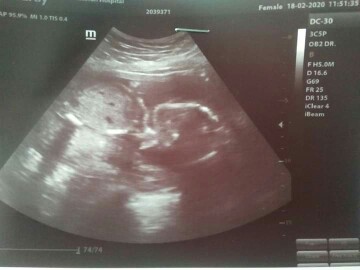

แฝดชายหญิง28ก.ค.คะ